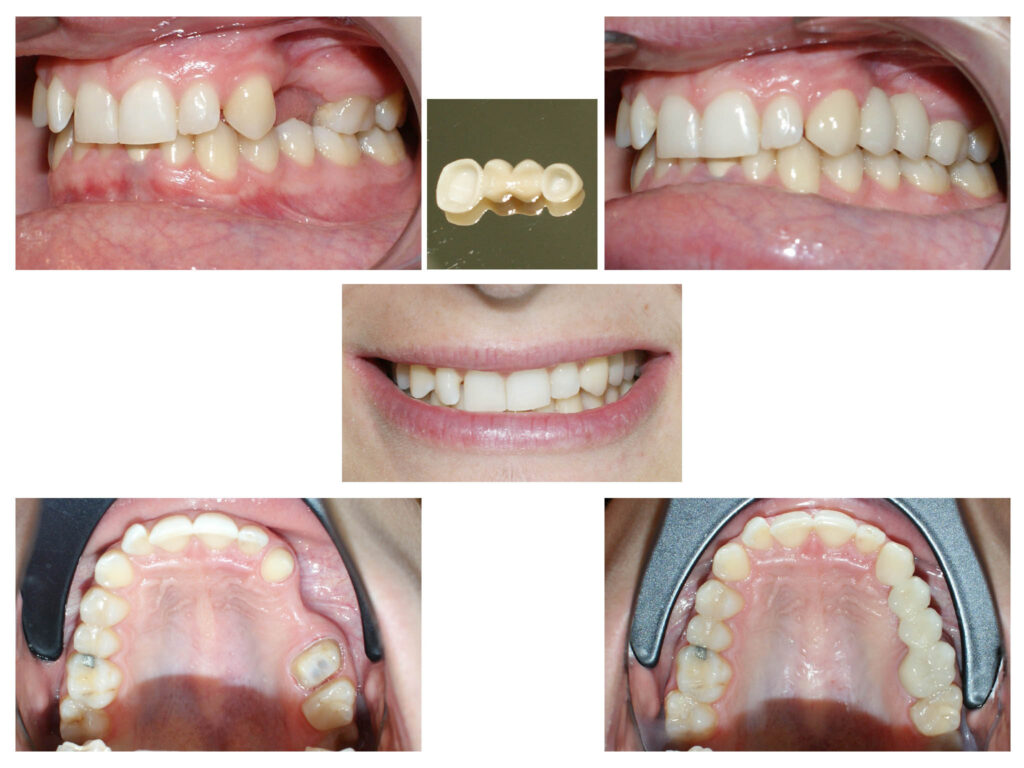

Un caz de o dificultate estestică majoră pe care l-am rezolvat cu succes împreună cu tehnicienii noștri. Am reușit să salvăm toți dinții deși erau destul de mult afectați și ulterior să îi îmbracăm cu coroane solo. Cromatica coronițelor este atât de potrivită încât în final nu se diferențiază de dinții naturali printre care sunt intercalate